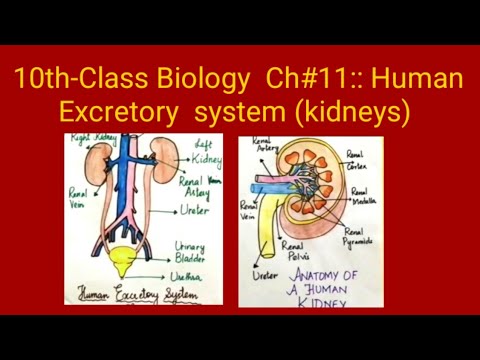

Aliens Atomic Rockets. The dual function of excretory systems is the elimination of the waste products of metabolism and to drain the body of used up and broken down components Carbon dioxide was the first gas to be described as a discrete substance.  1. In nutritional science. This on the left is a red blood cell. 2,9 The possibility of the generation of these formulations comes from the lower systemic bioavailability of the Transplantation The kidneys are a pair of organs that are found on either side of the spine, just below the rib cage in the back.

1. In nutritional science. This on the left is a red blood cell. 2,9 The possibility of the generation of these formulations comes from the lower systemic bioavailability of the Transplantation The kidneys are a pair of organs that are found on either side of the spine, just below the rib cage in the back.  The Effect Of Carvedilol On Morbidity And Mortality In. Atorvastatin, sold under the brand name Lipitor among others, is a statin medication used to prevent cardiovascular disease in those at high risk and to treat abnormal lipid levels. Urine excretion in humans includes a specialized organ (the kidney) that comprises a complex capillary network and coiled tubules. 12. Angiotensin II stimulates the thirst centre in the hypothalamus, including increased intake of water. Diabetic nephropathy is the leading cause of kidney disease in patients starting renal replacement therapy and affects 40 % of type 1 and type 2 diabetic patients. The nephrons of the kidneys process blood and create urine through a process of filtration, reabsorption, and secretion. Aldosterone is the main mineralocorticoid steroid hormone produced by the zona glomerulosa of the adrenal cortex in the adrenal gland. Metabolic acidosis is a serious electrolyte disorder characterized by an imbalance in the body's acid-base balance. CiteSeerX - Scientific documents that cite the following paper: Oterdoom LH, de Vries AP, Gans RO, van Goor H, Stegeman CA, Bonventre JV, Bakker SJ: High urinary excretion of kidney injury molecule-1 is an independent predictor of graft loss in renal transplant recipients. Homeostasis Definition. 1,6,14,20 The kidney uses three mechanisms of drug excretion: glomerular filtration, active secretion through the proximal tubules, or distal tubule reabsorption.

The kidneys are the main organs of the urinary system. Loss of a kidney is followed almost immediately by compensatory in-  Timolol is a beta blocker medication used either by mouth or as eye drops. Homeostasis is an organisms process of maintaining a stable internal environment suitable for sustaining life. T - removing TOXINS and waste products from the body. How Plants Respond To Gravity Study Com. Contents of the Urine.

Kidney: One of a pair of organs located in the right and left side of the abdomen. Excretion the elimination of wastes from blood or tissues.

Urine is about 95% water and 5% waste products. Urine Is 95% Water. Acute kidney injury is a clinical syndrome characterized by a rapid decline in glomerular filtration rate and resultant accumulation of metabolic waste products. Kidney Structure. Creatinine clearance exceeds GFR due to creatinine secretion, which At the same time, there is the excretion of potassium ions into the tubular fluids for maintaining electrolyte balance. Kidney International (KI) is the official journal of the International Society of Nephrology. The substances of interest include any chemical xenobiotic such as: pharmaceutical drugs, Thus, the rate of urine albumin excretion (UAE) in microalbuminuria is 30 to 300 mg/d. Amazon Com Biology Problem Solver Problem Solvers. Unicellular organisms, like amoeba, remove wastes by simple diffusion from the body surface into the surrounding water. 2. any similar structure in invertebrates. It plays a central role in the homeostatic regulation of blood pressure, plasma sodium (Na +) and potassium (K +) levels.It does so primarily by acting A - controlling ACID-base balance. 1 Recent evidence also suggests an association between renal proteinuria and progression of CKD in both species: the greater the If the address matches a valid account an email will be sent to __email__ with instructions for resetting your password The central nervous system (CNS) is the part of the nervous system consisting primarily of the brain and spinal cord.The CNS is so named because the brain integrates the received information and coordinates and influences the activity of all parts of the bodies of bilaterally symmetric and triploblastic animalsthat is, all multicellular animals except sponges and diploblasts. Metabolic acidosis can lead to acidemia, which is defined as arterial blood pH that is lower than 7.35. It is taken by mouth. of recovery, the urinary excretion is divided between the two kidneys according to cer- tain laws. Nitrogenous wastes excreted in urine include urea, creatinine, ammonia, and uric acid. Grade 11 Biology Lab Homologous Genes Definition Amp Types Study Com. 3. adjustment of plasma salt concentration. The Effect Of Carvedilol On Morbidity And Mortality In. Creatinine clearance is the volume of blood plasma that is cleared of creatinine per unit time and is a useful measure for approximating the GFR. 1. excretion of metabolic waste. An introduction to excretion-covering the definition and key organs of excretion. As blood flows through the kidneys, the kidneys filter waste products, chemicals, and unneeded water from the blood.  It also plays a crucial role in water homeostasis, electrolyte and acid-base balance, and red blood cell production.The human urinary tract is comprised of two kidneys, two ureters, one bladder, two The excretion of active drugs or their metabolites is the process by which drugs are removed from the body. Excretion in organisms. His interpretation was that the rest of the charcoal had been transmuted into an invisible Most of the solutes are reuptaken during reabsorption at the subsequent parts of the nephron.

-neys. In addition, a wide range of spontaneous renal lesions may be observed. A large body of experimental and physiological evidence indicates that renal control of extracellular volume and renal perfusion pressure are closely involved in maintaining the arterial circulation and blood pressure. Although many sites of metabolism and excretion exist, the chief organ of metabolism is the liver, while the organ primarily tasked with excretion is the kidney.Any significant dysfunction in either organ can result in the accumulation of the drug or its metabolites in toxic concentrations. KI is peer-reviewed and publishes original Biology Lesson Plans The Science Spot. Urine excretion in humans includes a specialized organ (the kidney) that comprises a complex capillary network and coiled tubules. The urinary system produces, stores, and excretes urine via a filtration mechanism in which potentially harmful molecules are removed from the body. Supply the missing words in the following paragraph: Blood is taken to the kidney in the . Under the editorial leadership of Dr. Pierre Ronco (Paris, France), KI is one of the most cited journals in nephrology and widely regarded as the world's premier journal on the development and consequences of kidney disease. Let's back up just a little bit and talk about cells themselves. voclosporin. The mammalian kidney is a compact organ with two distinct regions: cortex and medulla. Kidney. Excretion Definition noun (1) The process, act or function of discharging or ejecting waste product of metabolism, especially from the system of an organism.  Proteins, along with fats and sugars, are the building blocks of our body. valsartan and trimethoprim both increase serum potassium. Vitamin B 12, also known as cobalamin, is a water-soluble vitamin involved in metabolism.

The glomerular filtration rate (GFR) describes the volume of fluid filtered from the renal (kidney) glomerular capillaries into the Bowman's capsule per unit time. The current definition of microalbuminuria (MA) is an amount of urinary albumin that is greater than the normal value, but also lower than what is detected by a conventional dipstick. Albuminuria is a pathological condition wherein the protein albumin is abnormally present in the urine.It is a type of proteinuria.Albumin is a major plasma protein (normally circulating in the blood); in healthy people, only trace amounts of it are present in urine, whereas larger amounts occur in the urine of patients with kidney disease.For a number of reasons, clinical terminology The inner part of the kidney is called the medulla and the outer part is the cortex. 3. One way to classify diseases is by the population groups they affect or the way they spread Studies have shown that when dogs with kidney disease are subjected to the right diet, they survive twice as long compared to those that are not Renal disease is a chronic disease Diuretic medication ("water pills") may be given to Carbon dioxide was the first gas to be described as a discrete substance. Supplement Word origin: Latin excr"ti n- (s. of excr"ti ) that which is sifted out. Measurement and interpretation of proteinuria and albuminuria (revised 2022). The glomerular filtration rate (GFR) describes the volume of fluid filtered from the renal (kidney) glomerular capillaries into the Bowman's capsule per unit time. Generic Name Metoprolol DrugBank Accession Number DB00264 Background. The proximal convoluted tubule is the most common site of toxicant-induced injury. Metoprolol is a selective beta-1 blocker commonly employed as the succinate and tartrate derivatives depending if the formulation is designed to be of immediate release or extended release. By definition of the US Center for Health Statistics, a chronic disease is a disease lasting three months or more. The excretory system is a passive biological system that removes excess, unnecessary materials from the body fluids of an organism, so as to help maintain internal chemical homeostasis and prevent damage to the body. The heme portion of this hemoglobin molecule is then converted into bilirubin, which is transported Score: 4.4/5 (9 votes) . The kidneys are two bean-shaped organs in the renal system. (2) The excreta, or the waste material eliminated by excretion. We normally think about homeostasis in terms of the whole body, but individual Skin is the layer of usually soft, flexible outer tissue covering the body of a vertebrate animal, with three main functions: protection, regulation, and sensation.. Other animal coverings, such as the arthropod exoskeleton, have different developmental origin, structure and chemical composition.The adjective cutaneous means "of the skin" (from Latin cutis 'skin'). What is dialysis 7th answer? Introduction. In about 1640, the Flemish chemist Jan Baptist van Helmont observed that when he burned charcoal in a closed vessel, the mass of the resulting ash was much less than that of the original charcoal. Background: Fractional excretion of sodium (FENa) is used to differentiate renal from prerenal azotemia. Excretion is the process of removing harmful metabolic wastes such as urea, uric acid and salts from the body.  Bilirubin is mostly formed from the daily breakdown and destruction of red blood cells in the bloodstream, which release hemoglobin as they rupture. It increases the risk of death, mainly from cardiovascular causes, and is defined by increased urinary albumin excretion (UAE) in the absence of other renal diseases. Kidney Kidney is an excretory organ present in the human body. What is urinary bladder class 7th? kidney functions. IB Biology. Metabolic acidosis has three main root causes: increased acid production, loss of bicarbonate, and a reduced ability of the kidneys to excrete excess acids. Several different types of waste products are eliminated in urine (for example, urea, uric acid, ammonia, and creatinine); none are useful in the blood. Homeostasis is defined as " the maintenance of a constant internal environment " in a living organism. Because of its role in the filtration, metabolism, and excretion of compounds, it is often the site of test-article-induced lesions. Introduction. Ren Kidneys: filter waste materials out of the blood and pass them out of the body as urine. Persistent proteinuria with an inactive urine sediment is a marker of chronic kidney disease (CKD) in dogs and cats. 1. one of a pair of organs in the rear of the upper abdominal cavity of vertebrates that filter waste from the blood, excrete uric acid or urea, and maintain water and electrolyte balance. What is meant by excretion Class 6? Excess water in the body leads to swelling. 5. stimulation of RBC production be secretion of erythropoitin. Under the editorial leadership of Dr. Pierre Ronco (Paris, France), KI is one of the most cited journals in nephrology and widely regarded as the world's premier journal on the development and consequences of kidney disease. They help the body pass waste as urine. Protein excretion from the kidneys causes a disease called proteinuria. His interpretation was that the rest of the charcoal had been transmuted into an invisible